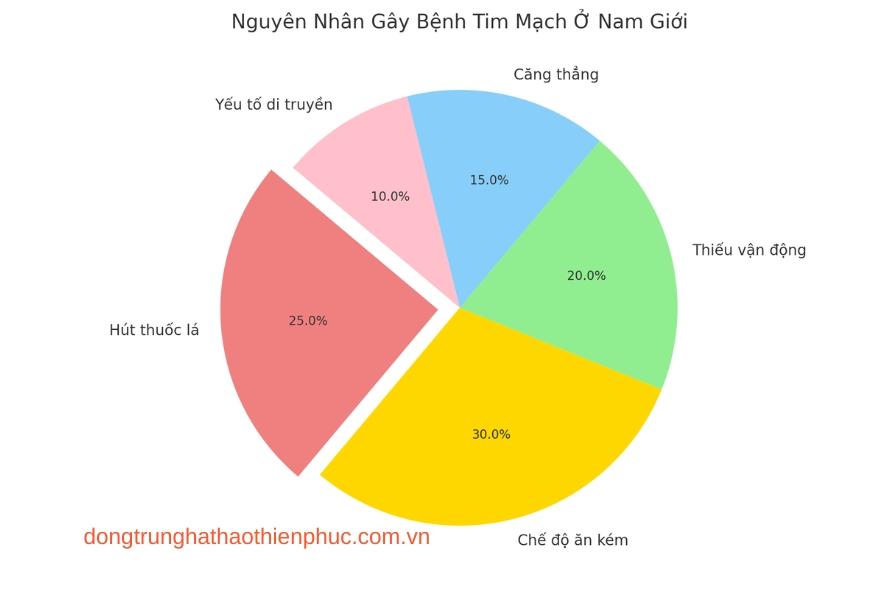

Bệnh tim mạch là một trong những nguyên nhân gây tử vong hàng đầu ở nam giới trên toàn thế giới. Những thay đổi trong lối sống hiện đại, cùng với áp lực công việc và các thói quen không lành mạnh, khiến nam giới dễ mắc phải các vấn đề về tim mạch. Trong bài viết này, chúng ta sẽ cùng tìm hiểu bệnh tim mạch ở nam giới, các nguyên nhân, triệu chứng và cách phòng ngừa hiệu quả.